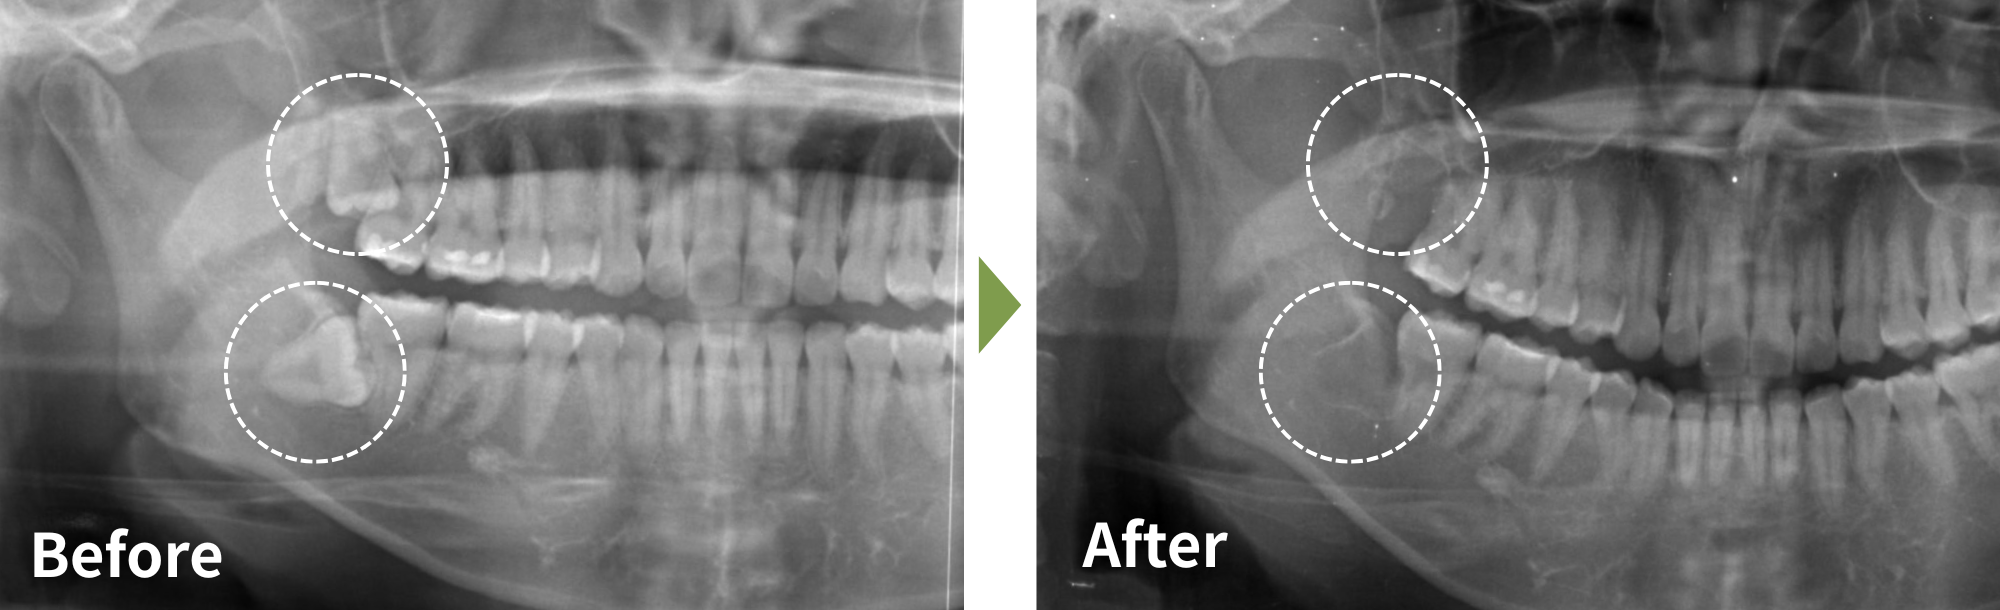

| 治療名 | 下顎の親知らず(完全埋伏智歯)抜歯術 |

|---|---|

| 患者様情報 | 30代女性 |

| 執刀医 | Dr. 井出 |

| 治療内容 |

他院で治療中の患者様。担当医より下顎親知らずの抜歯を勧められたが、低位埋伏かつ下顎管との接触が疑われたため、大学病院での抜歯を提案された。 日帰りでの抜歯を希望され、当院のホームページを見て来院。 |

| 症例写真 |

|

| 治療期間 | 約30分 |

| 治療経過 |

抜歯後1週間で抜糸を行い、痛みや腫れは改善。 下歯槽神経に近接していたが、神経麻痺などの症状は認められず、経過良好。 |

| 一般的なリスク・副作用 | 腫れ、痛み、出血、感染、下唇やあごのしびれなどの神経麻痺が生じる場合があります。 |